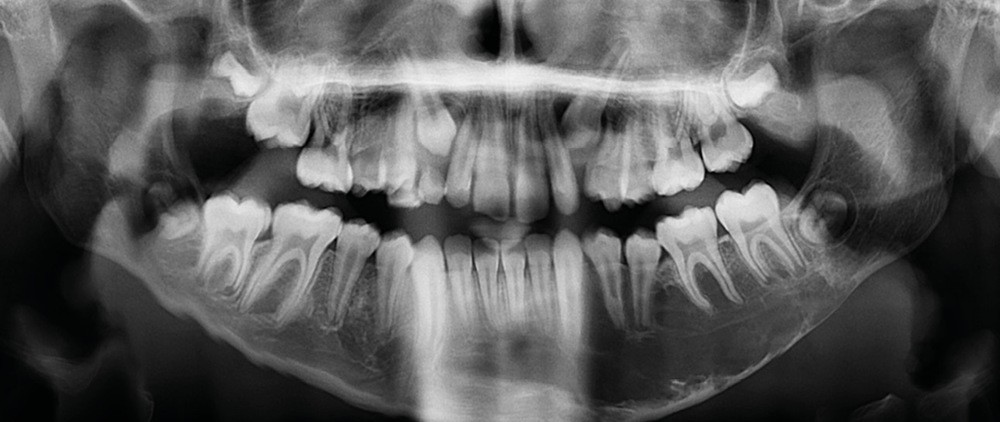

Il existe une zone ostéolytique unique, aux contours extrêmement fins, évidant la branche horizontale de la mandibule, et dont la limite supérieure est mieux marquée et dite « circinée », contournant les racines dentaires.